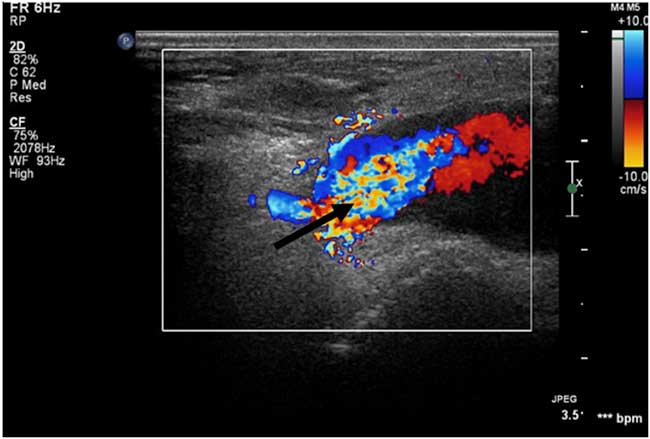

Duplex ultrasound performed in the radiology suite the following morning (eighth day after initial injury) revealed a left anterior tibial artery pseudoaneurysm at the level of the ankle measuring 2.94×1.86 cm, with a 5.6×1.9 cm hematoma overlying the lateral ankle (Figures 2 and 3). Diagnostic ultrasound images of the lesion were obtained by scanning over skin marked with the large X (Figure 1), corresponding to the area of maximal swelling and pain. Distal flow was identified within the dorsalis pedis artery. The diagnosis was confirmed with CT angiography, which demonstrated a large pseudoaneurysm arising from the dorsal-lateral aspect of the proximal dorsalis pedis artery. Of note, after imaging the patient was re-examined and found to have an easily audible bruit in the area of the anterolateral ankle and dorsum of the foot, overlying the pseudoaneurysm.

Figure 3 Colour Doppler ultrasound image of this patient’s pseudoaneurysm. Blue = blood flow toward probe, Red = blood flow away from probe, Arrow = area of high-velocity swirling.

While angiography remains the gold standard for diagnosis and treatment planning, duplex ultrasound is the accepted modality for initial non-invasive imaging.Reference Shah, Fischman and Marin 11 , Reference Webber, Jang and Gustavson 16 Sensitivity and specificity of duplex ultrasonography in the diagnosis of pseudoaneurysm are estimated at 94% and 97%, respectively.Reference Coughlin and Paushter 19 Bedside diagnosis of post-traumatic arterial pseudoaneurysms of the face and lower limb, using point-of-care ultrasonography performed by the ED physician, has indeed been described in a few case reports of single patients.Reference Goksu, Kucukyilmaz and Soyuncu 18 , Reference Goksu, Yuruktumen and Kaya 20 - Reference Jenq, Panebianco and Lee 22 The bedside technique most commonly described consists of linear ultrasound probe placement directly over the area of maximal swelling (or bruit/thrill, if present).Reference Goksu, Kucukyilmaz and Soyuncu 18 , Reference Goksu, Yuruktumen and Kaya 20 The anechoic pseudoaneurysm cavity may be pulsatile and is commonly surrounded by hypoechoic thrombus (Figure 2).Reference Goksu, Kucukyilmaz and Soyuncu 18 , Reference Jenq, Panebianco and Lee 22 This sonographic appearance may closely resemble that of an abscess cavity with debris.Reference Abdi, Armijo and Seif 21 The use of color Doppler is particularly valuable in differentiating the two. Characteristic findings of pseudoaneurysm include bidirectional blood flow in the pseudoaneurysm neck, pulsatile flow in the cavity (Figure 3), and the “yin-yang sign” (swirling blood in the pseudoaneurysm resembling the ancient symbol).Reference Goksu, Yuruktumen and Kaya 20 The accuracy of bedside ultrasound in the diagnosis of arterial pseudoaneurysms has not yet been elucidated.